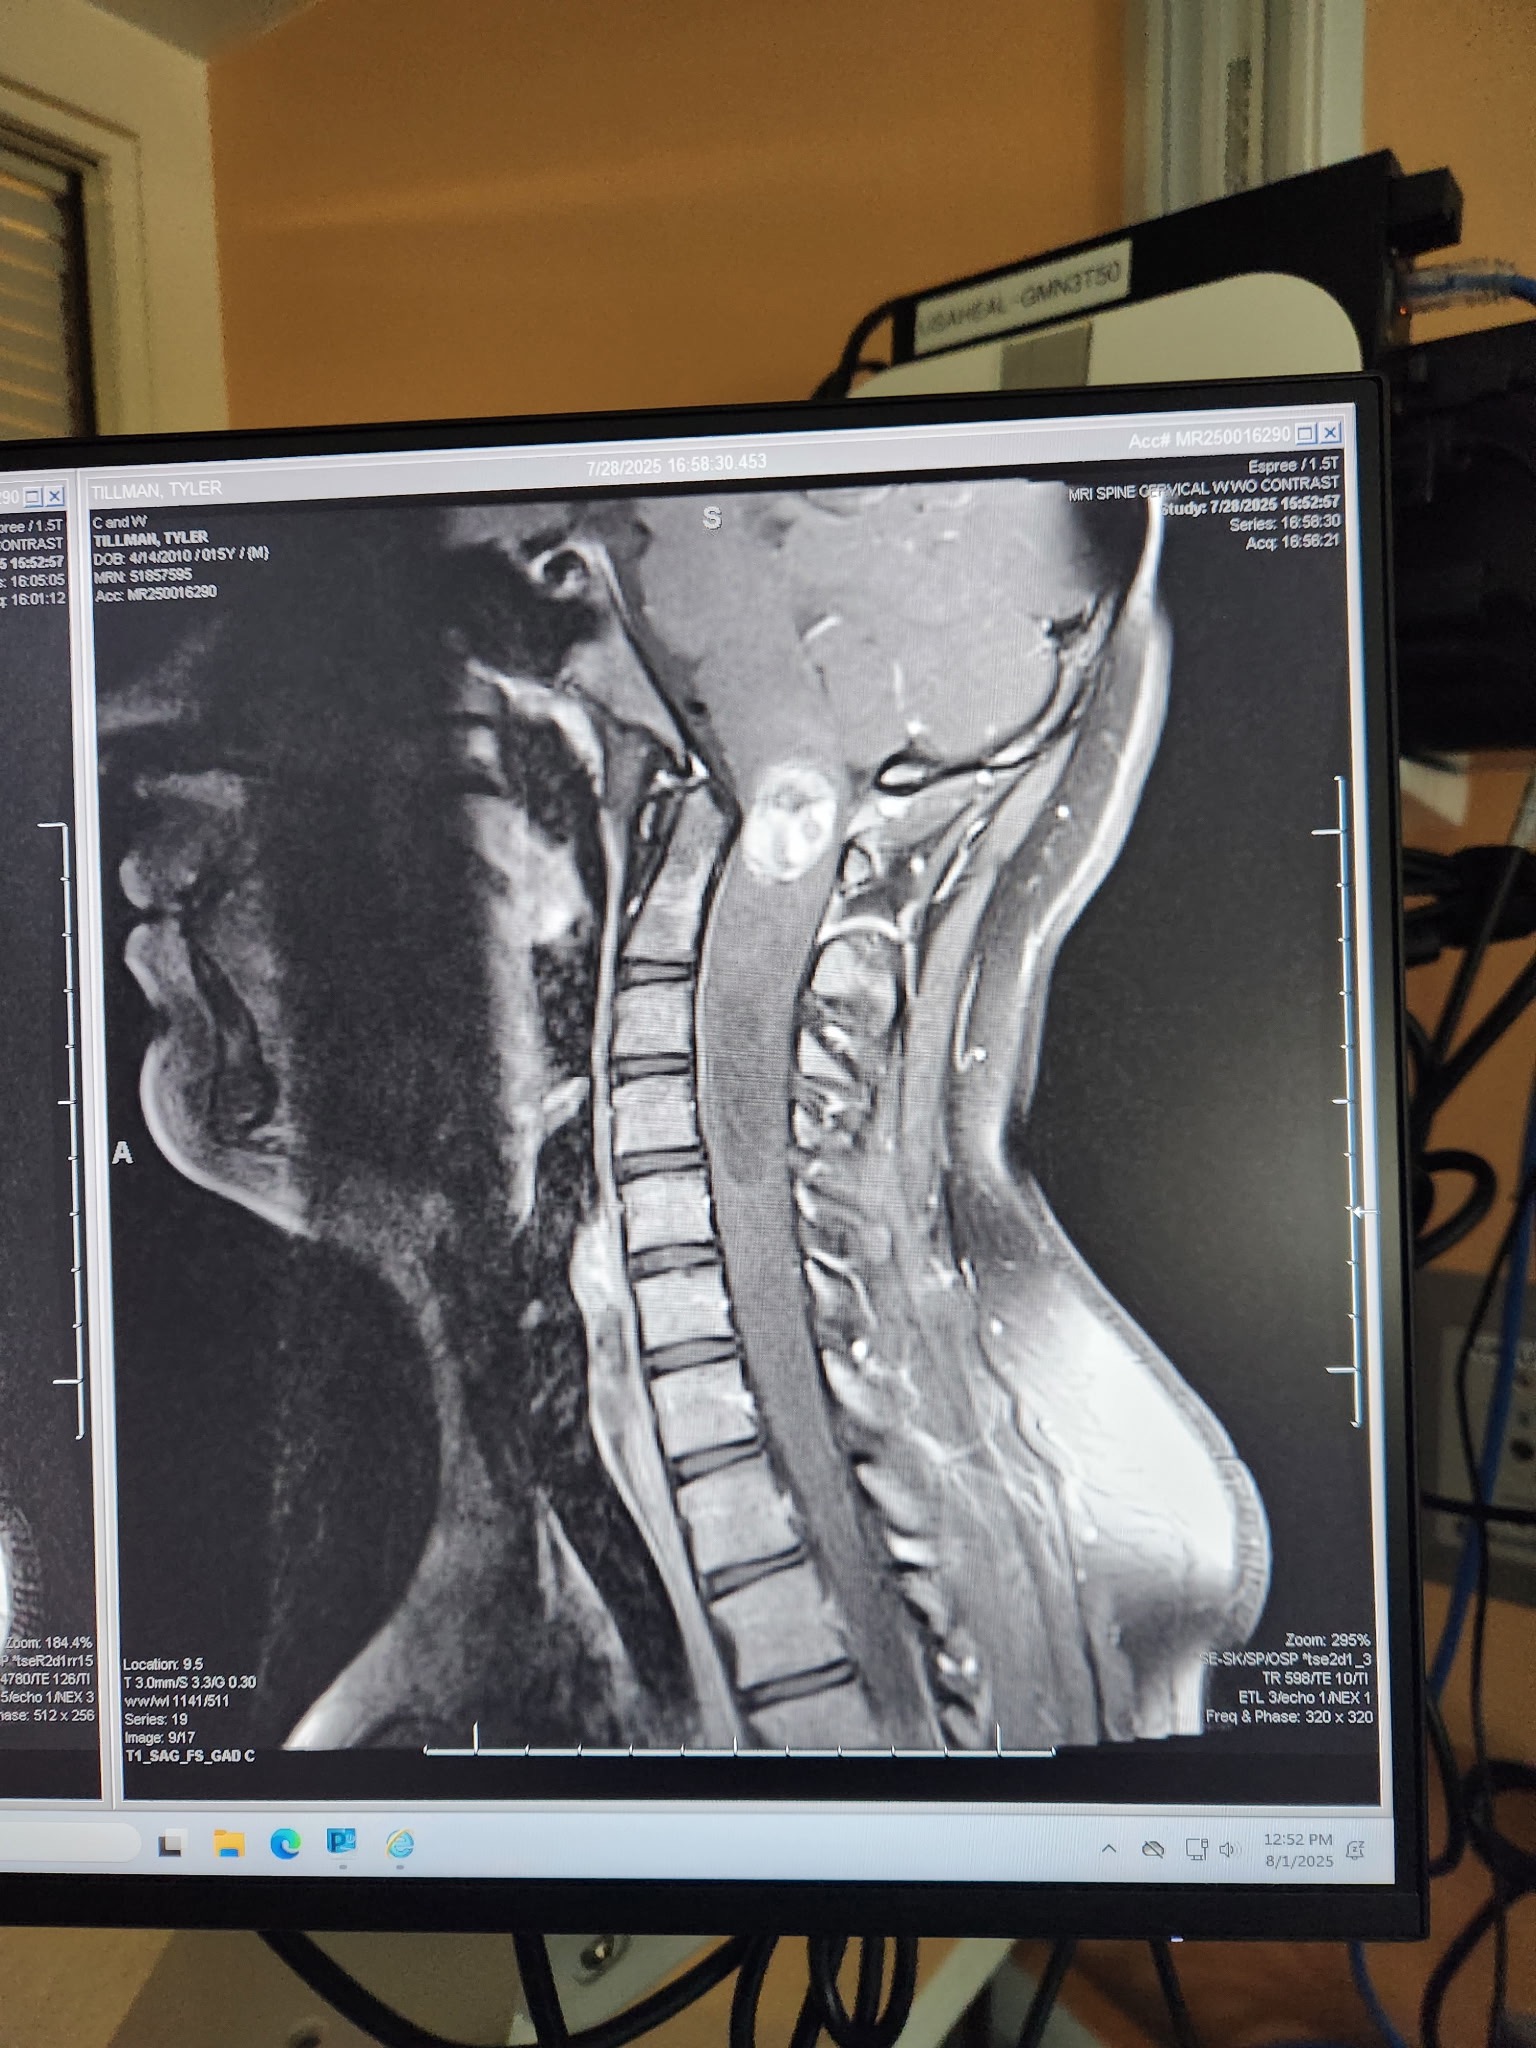

Tyler was recently diagnosed with a tumor on his brain stem — one of the most delicate and critical areas of the brain. He is scheduled to undergo major brain surgery this coming Monday.